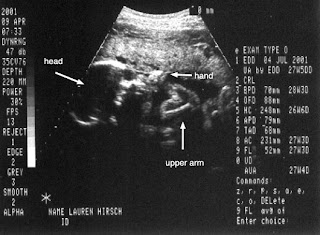

Lauren is twenty seven weeks, five days. Ultrasound shows the baby right on schedule. The baby weighs approximately 2 pounds, 7 oz so far, and is looking great. Here is a picture of the baby's legs and head, right hand and arm. Oh, and the doctor is now quite certain we've got a girl.